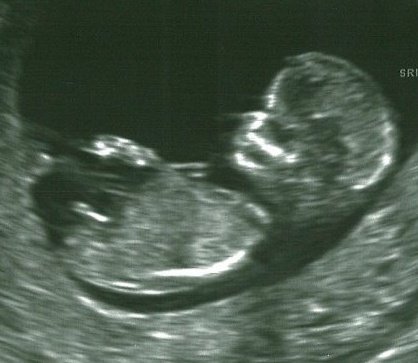

Had NT Scan... Guess what I am????

I had my NT scan on Monday and it was so wonderful to get to see the baby for such a long period of time!!! Although my baby wasn't cooperating with the tech , we did get some really good pictures. She wouldn't guess the sex because the legs were crossed most of the time, and because the baby was curled. She did, however, say she saw a nub.... So... whats your guess boy or girl?? Image Attachment(s):

Nub is on an upward angle.

Thanks!!! I did post on ingender and got 100% boy responses!

I guess too because of the angle of the dangle!